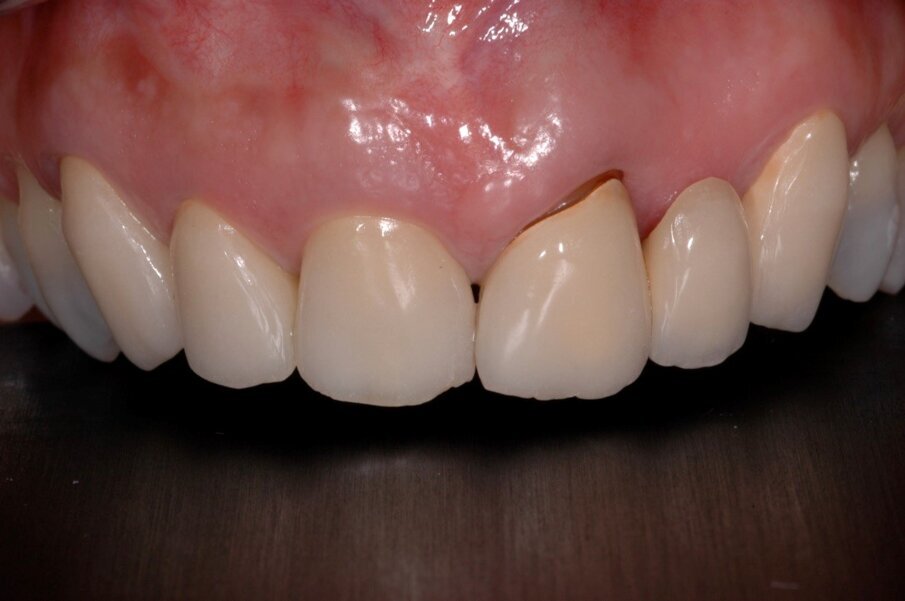

A questo punto veniva avvitato sull’impianto un moncone provvisorio, completato l’innesto di materiale biocompatibile con osso equino collagenato (OX granules, Bioteck) nel gap esistente tra la fixture e la lamina, poi veniva connessa al moncone provvisorio la corona provvisoria in resina (Fig. 13). La rx di controllo post intervento evidenzia la buona riuscita della procedura e la corretta connessione tra moncone e fixture (Fig. 14). Sei mesi più tardi alla rivalutazione e rimozione della corona provvisoria (Fig. 15) si può ben notare come questa procedura abbia permesso di mantenere integri i tessuti peri-implantari, di aver favorito la creazione di un tunnel mucoso spesso e maturo. I tessuti con e senza la corona provvisoria mostrano un aspetto naturale e le caratteristiche di una gengiva in salute (Figg. 16a, 16b).

La finalizzazione del caso ha previsto poi il rifacimento della vecchia corona su 12 insieme a quella su 11 in zirconia stratificata, progettata con il CAD/CAM, favorendo così il ripristino della funzione e dell’estetica laddove una complicanza aveva compromesso il risultato ottenuto dieci anni prima (Figg. 17-19). Sei mesi dopo l’intervento si può ben vedere come clinicamente e radiologicamente si sia ottenuto un buon successo bilogico ed estetico (Figg. 20-22).